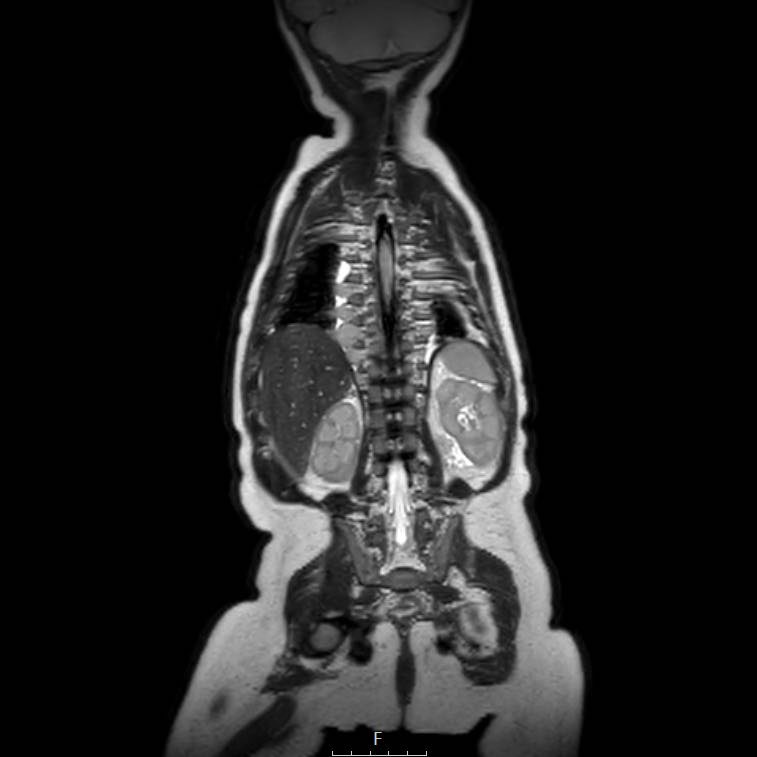

Cuộn qua chuỗi ảnh T2 theo mặt phẳng coronal.

Nghiên cứu các hình ảnh và sau đó tiếp tục đọc.

The findings are:

- Mass with encasement of the aorta and splanchnic vessels.

- Lan rộng dọc theo cột sống ngực nhưng không xâm lấn vào ống sống.

- Small liver metastases.

- Left supraclavicular mass.

Same patient.